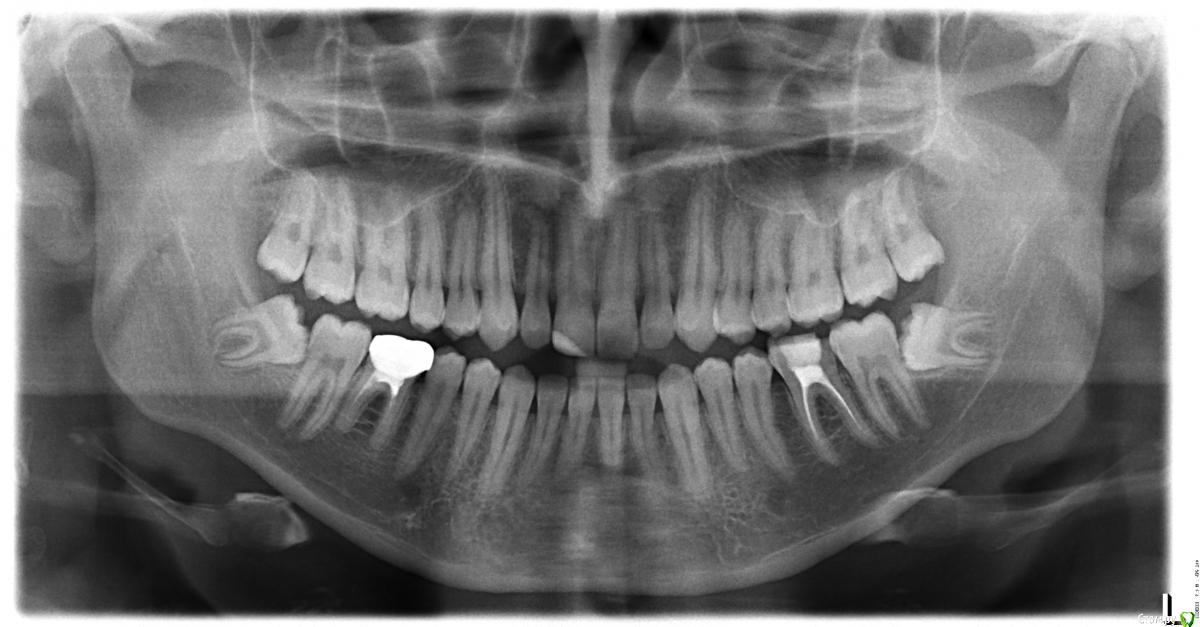

Дмитрий13 Опубликовано 29 июня, 2015 Поделиться Опубликовано 29 июня, 2015 Здравствуйте, уважаемые доктора!Сделал панорамный снимок. Буду признателен, если вы подскажете, какие зубы нуждаются во внимании.Спасибо! Ссылка на комментарий

AlexanderGudkov Опубликовано 29 июня, 2015 Поделиться Опубликовано 29 июня, 2015 Зубы мудрости нуждаются в внимании хирурга) Ссылка на комментарий

red_butler Опубликовано 29 июня, 2015 Поделиться Опубликовано 29 июня, 2015 Мудрые зубы удалять, снимать коронку с 4.6. Перелечивать и протезировать 3.6 4.6 Ссылка на комментарий